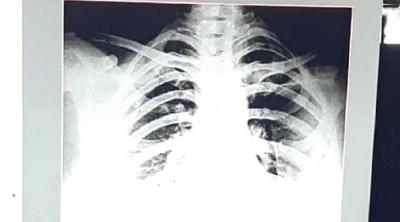

कोरोना व्हायरसच्या दुसऱ्या लाटेने थैमान घातलं आहे. अशात राजस्थानच्या कोटामधून एक धक्कादायक केस समोर आली आहे. इथे केवळ २४ तासात ३२ वर्षीय महिलेचे दोन्ही फुप्फुसं खराब झाले आहेत. फुप्फुसांचे एक्स--रे समोर आले आहेत.

ही केस आहे कोटामधील. येथील ३२ वर्षीय महिलेने ९ तारखेला एक्स-रे काढला तेव्हा ती ठीक होती. १२ तारखेपर्यंत महिल ठीक होती. बीपी, ऑक्सीजन लेव्हल, एक्स-रे सगळं काही ठीक होतं. त्यानंतर १ तारखेला रात्री तिला जरा घाबरल्यासारखं वाटू लागलं होतं.

महिला १३ तारखेला उभीही राहू शकत नव्हती. तिला श्वास घेण्यास त्रास होता होता. ऑक्सीजन लेव्हल चेक केलं तर ९४ होतं. १३ तारखेला सिटी स्कॅन केला तर तिचे दोन्ही फुप्फुसांमध्ये ८० टक्के इन्फेक्शन झालेलं होतं.

हे बघून कोटाचे श्वास रोग तज्ज्ञ डॉक्टर के के डंग हे हैराण झाले. कारण केवळ २४ तासात तिची फुप्फुसे खराब झाली होती. त्यांनी इंदुरच्या एका डॉक्टरसोबत याबाबत चर्चा केली तर त्यांनी सांगितले की, हा नवा स्ट्रेन आहे ज्यामुळे असं झालंय.